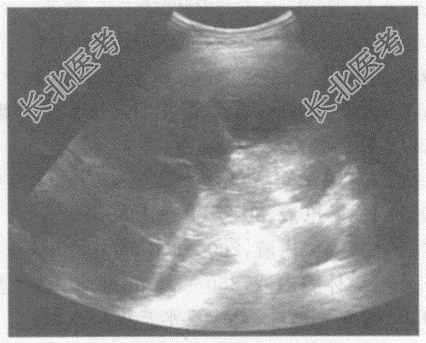

- 单项选择题临床资料:女性患者, 53岁,自述胸闷不适月余。

超声综合描述: 左侧胸腔内可见大片状无回声区,呈网格状, 最大深度4.8cm;其上方胸膜厚度1.1cm, 边缘欠规整。

超声提示: A、左肺脓肿

B、左侧胸腔积液(内见分隔)左侧胸膜增厚

C、左侧胸腔包裹性积液

D、左膈下积液

E、左肺囊性占位